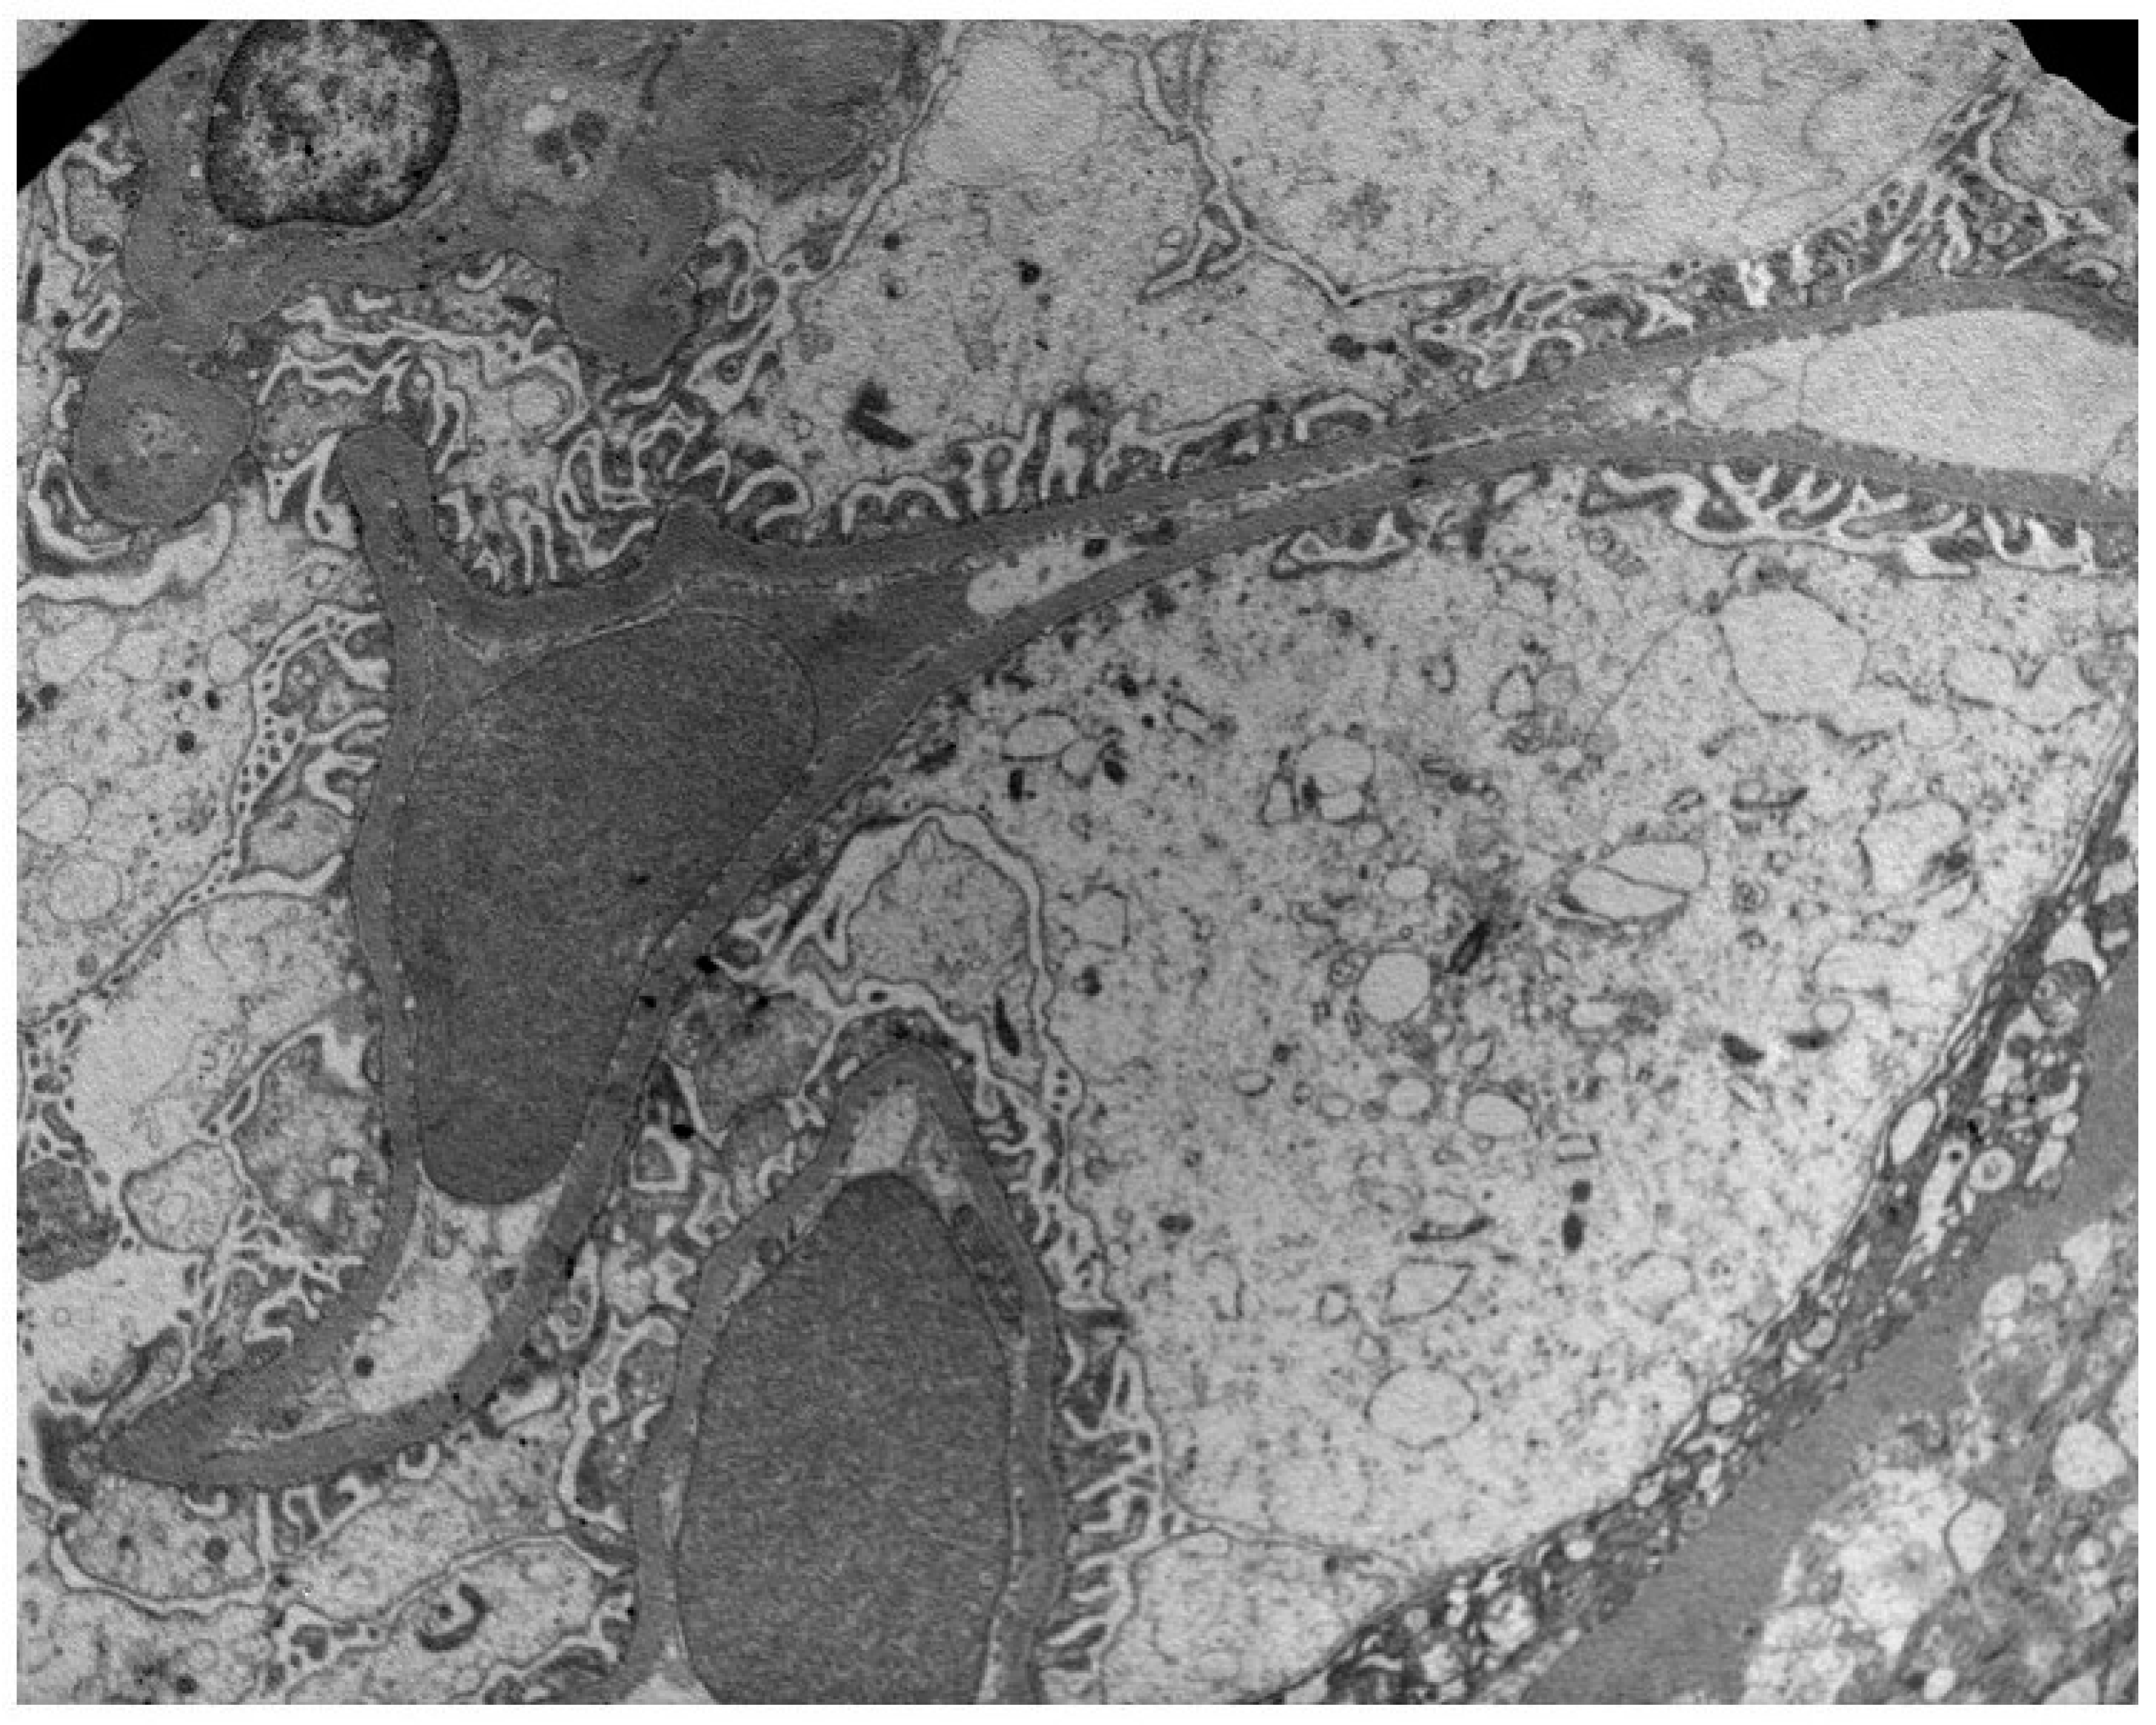

Patients with global podocyte foot process fusion (n = 11) had a higher mean urine PDC value, 99.331 ng/mL, compared to those with segmental fusion (n = 26), with a PDC value of 58.88 ng/mL and compared to the controls (Figure 1 and Figure 2). Moreover, in patients with fibrillary structures (n = 3), we recorded significantly higher PDC levels (p = 0.009) and a statistically significant correlation between the PDC/CR ratio and the presence of fibrils (p = 0.01). In non-immune-complex-mediated glomerulonephritis, such as minimal change disease and FSGS [9], NEP/CR (coef ±SE [95% CI], −0.69 ± 0.33 [−1.36 to −0.02], p =0.042), The NEP/CR ratio was also associated with segmental podocyte foot process fusion (Table 3).

Figure 1.

Preservation of podocyte foot processes in a patient with low PDC (29 ng/mL) and NEP (32 ng/mL) urine concentrations.

Figure 2.

GBM thickening (arrow) in a patient with high PDC and NEP urine concentrations.